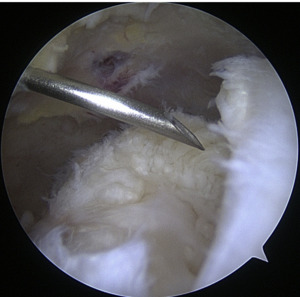

Instrumentation

When it comes to shoulder arthroscopy, the most common arthroscope utilized is the 4.0 mm 30 scope. A 30-magnification scope is sufficient for most situations. An arthroscopic-assisted coracoclavicular reconstruction, subscapularis repairs, Remplissage procedures, glenohumeral ligament lesions, and humeral avulsion can all benefit from the use of a 4.0-mm 70 arthroscope, which should always be on hand. There should be a large selection of cannulas accessible, and they will differ according on the operation being carried out.25

As the principal penetrating instruments, 5.5-mm blunt-tipped cannulas are often used for portal insertion. Blunt tips are preferred to reduce the likelihood of iatrogenic harm, especially to articular cartilage. Because they are easily passable by the majority of arthroscopy passing devices, 8.25-mm cannulas are often employed for “instrumentation” portals. In addition, cannulas of 6.5 mm or less are commonly used in suture management. Cannulas that are threaded or have locking mechanisms are preferable since they are less likely to come free from the joint. In most cases, one of two methods can be employed: gravity or a pump system. Sufficient management of pressures, usually approximately 60 mm Hg, is necessary to avoid significant soft-tissue edema, which can complicate the use of cannulas and instruments.25